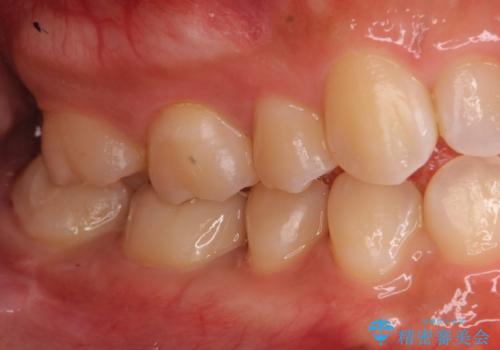

- 右下の保険治療での樹脂の劣化、および歯と歯の間の虫歯をセラミックのつめもので治療しました。

右下6番はセラミックのアンレーが入っていましたが、強度の問題もあり、やり直し後はクラウンとしました。